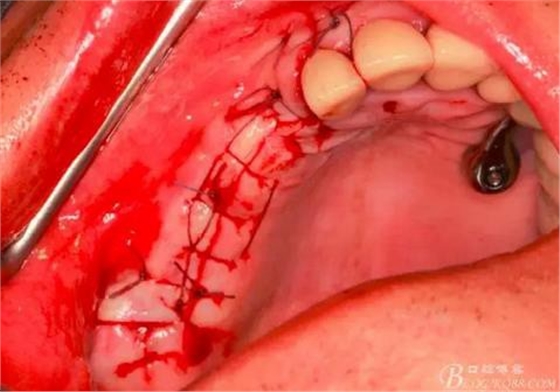

14,15牙位植入兩顆植體,6,7牙位骨高度嚴(yán)重不足,且骨密度低,無法給植體提供良好的初期穩(wěn)定性,需二期植入。13牙位骨寬度不足,沒有植骨、植植體,修復(fù)時用后面4顆連冠加一顆3的游離臂是沒有問題的。當(dāng)然這里我們不去討論這個方法的合理性,我們今天的話題是改良式外提升技術(shù)的應(yīng)用。

術(shù)后X光片。